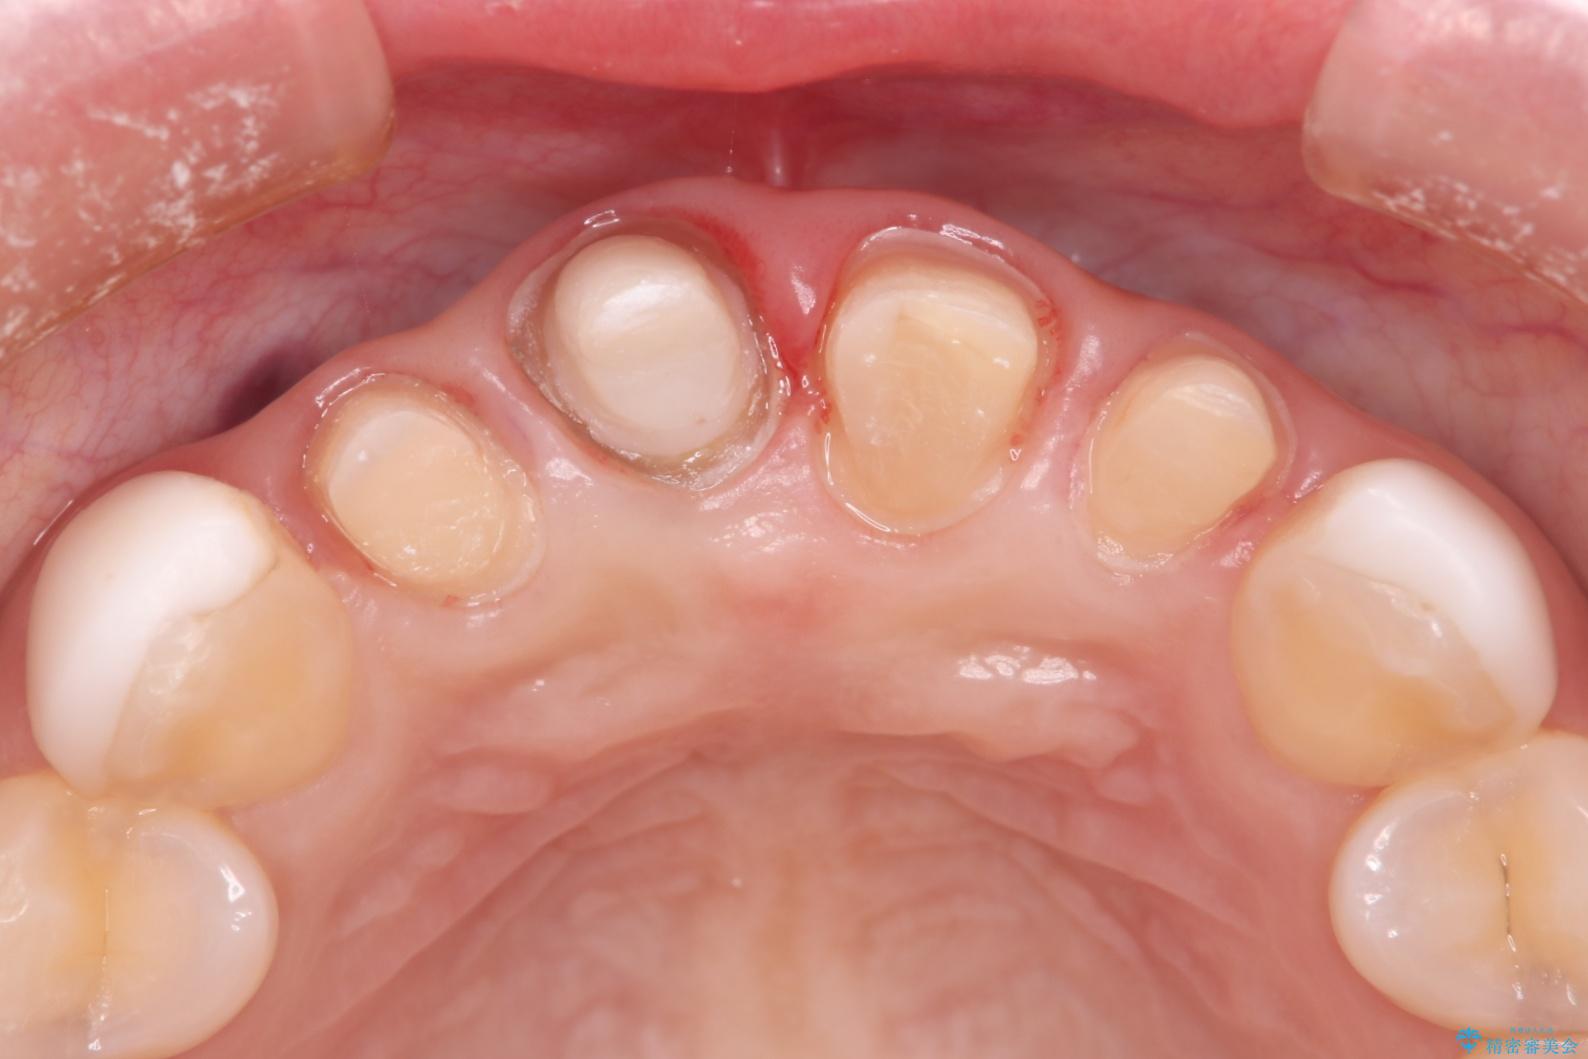

- 他院で治療した前歯の色が気になるということで来院された患者様です。前歯に色の差があり、レントゲンから内部にう蝕も見られたため、審美性に優れ、う蝕になりにくいオールセラミッククラウンで治療いたしました。

清掃性も上がったおかげで、歯肉の状態も良好に保てています。